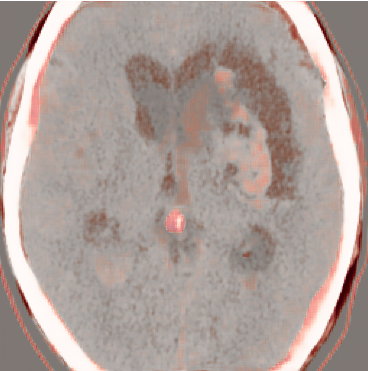

While ACAT revolves around generating counterfactuals, its primary strength lies in accurately identifying pathological regions, which are subsequently employed in a classification pipeline. On the other hand, it falls short in producing credible counterfactual examples, an issue we aim to address in this study. An illustration of this phenomenon is depicted in Figure 2, where we can observe how ACAT is able to generate a saliency map that approximately identifies the pathological region (e, bottom row). However, in the counterfactual example, the lesion remains visible (e, top row). In contrast, our approach not only refines the saliency map but also generates a counterfactual image where the pathology is completely eliminated (f).

ACAT addresses the limitations of the latent shift method in generating attribution maps; however, the counterfactual examples obtained through ACAT are not entirely satisfactory. In other words, ACAT is able to identify where an image should be modified, but not exactly how to modify it to obtain a credible counterfactual. This limitation is understandable since the primary focus of their paper was to utilise these saliency maps within a classification pipeline rather than generating precise counterfactuals.

4.3 Counterfactual Examples

In Figures 2 and 4 we display examples of healthy images and anomaly maps obtained with the different approaches. We can observe that f-Ano GAN is not able to generate credible counterfactuals and generally produces images of poor quality and unrealistic appearance. On the other hand, the approaches based on diffusion models are able to create more high-quality results. However, the ones obtained with CG and CFG seem to present some artifacts, which may not only impact the realism of the counterfactual examples but also the precision of the anomaly maps obtained from them. In order to better quantify the capability of these methods to accurately segment pathological areas, we compute the Dice scores of the anomaly maps they generate.